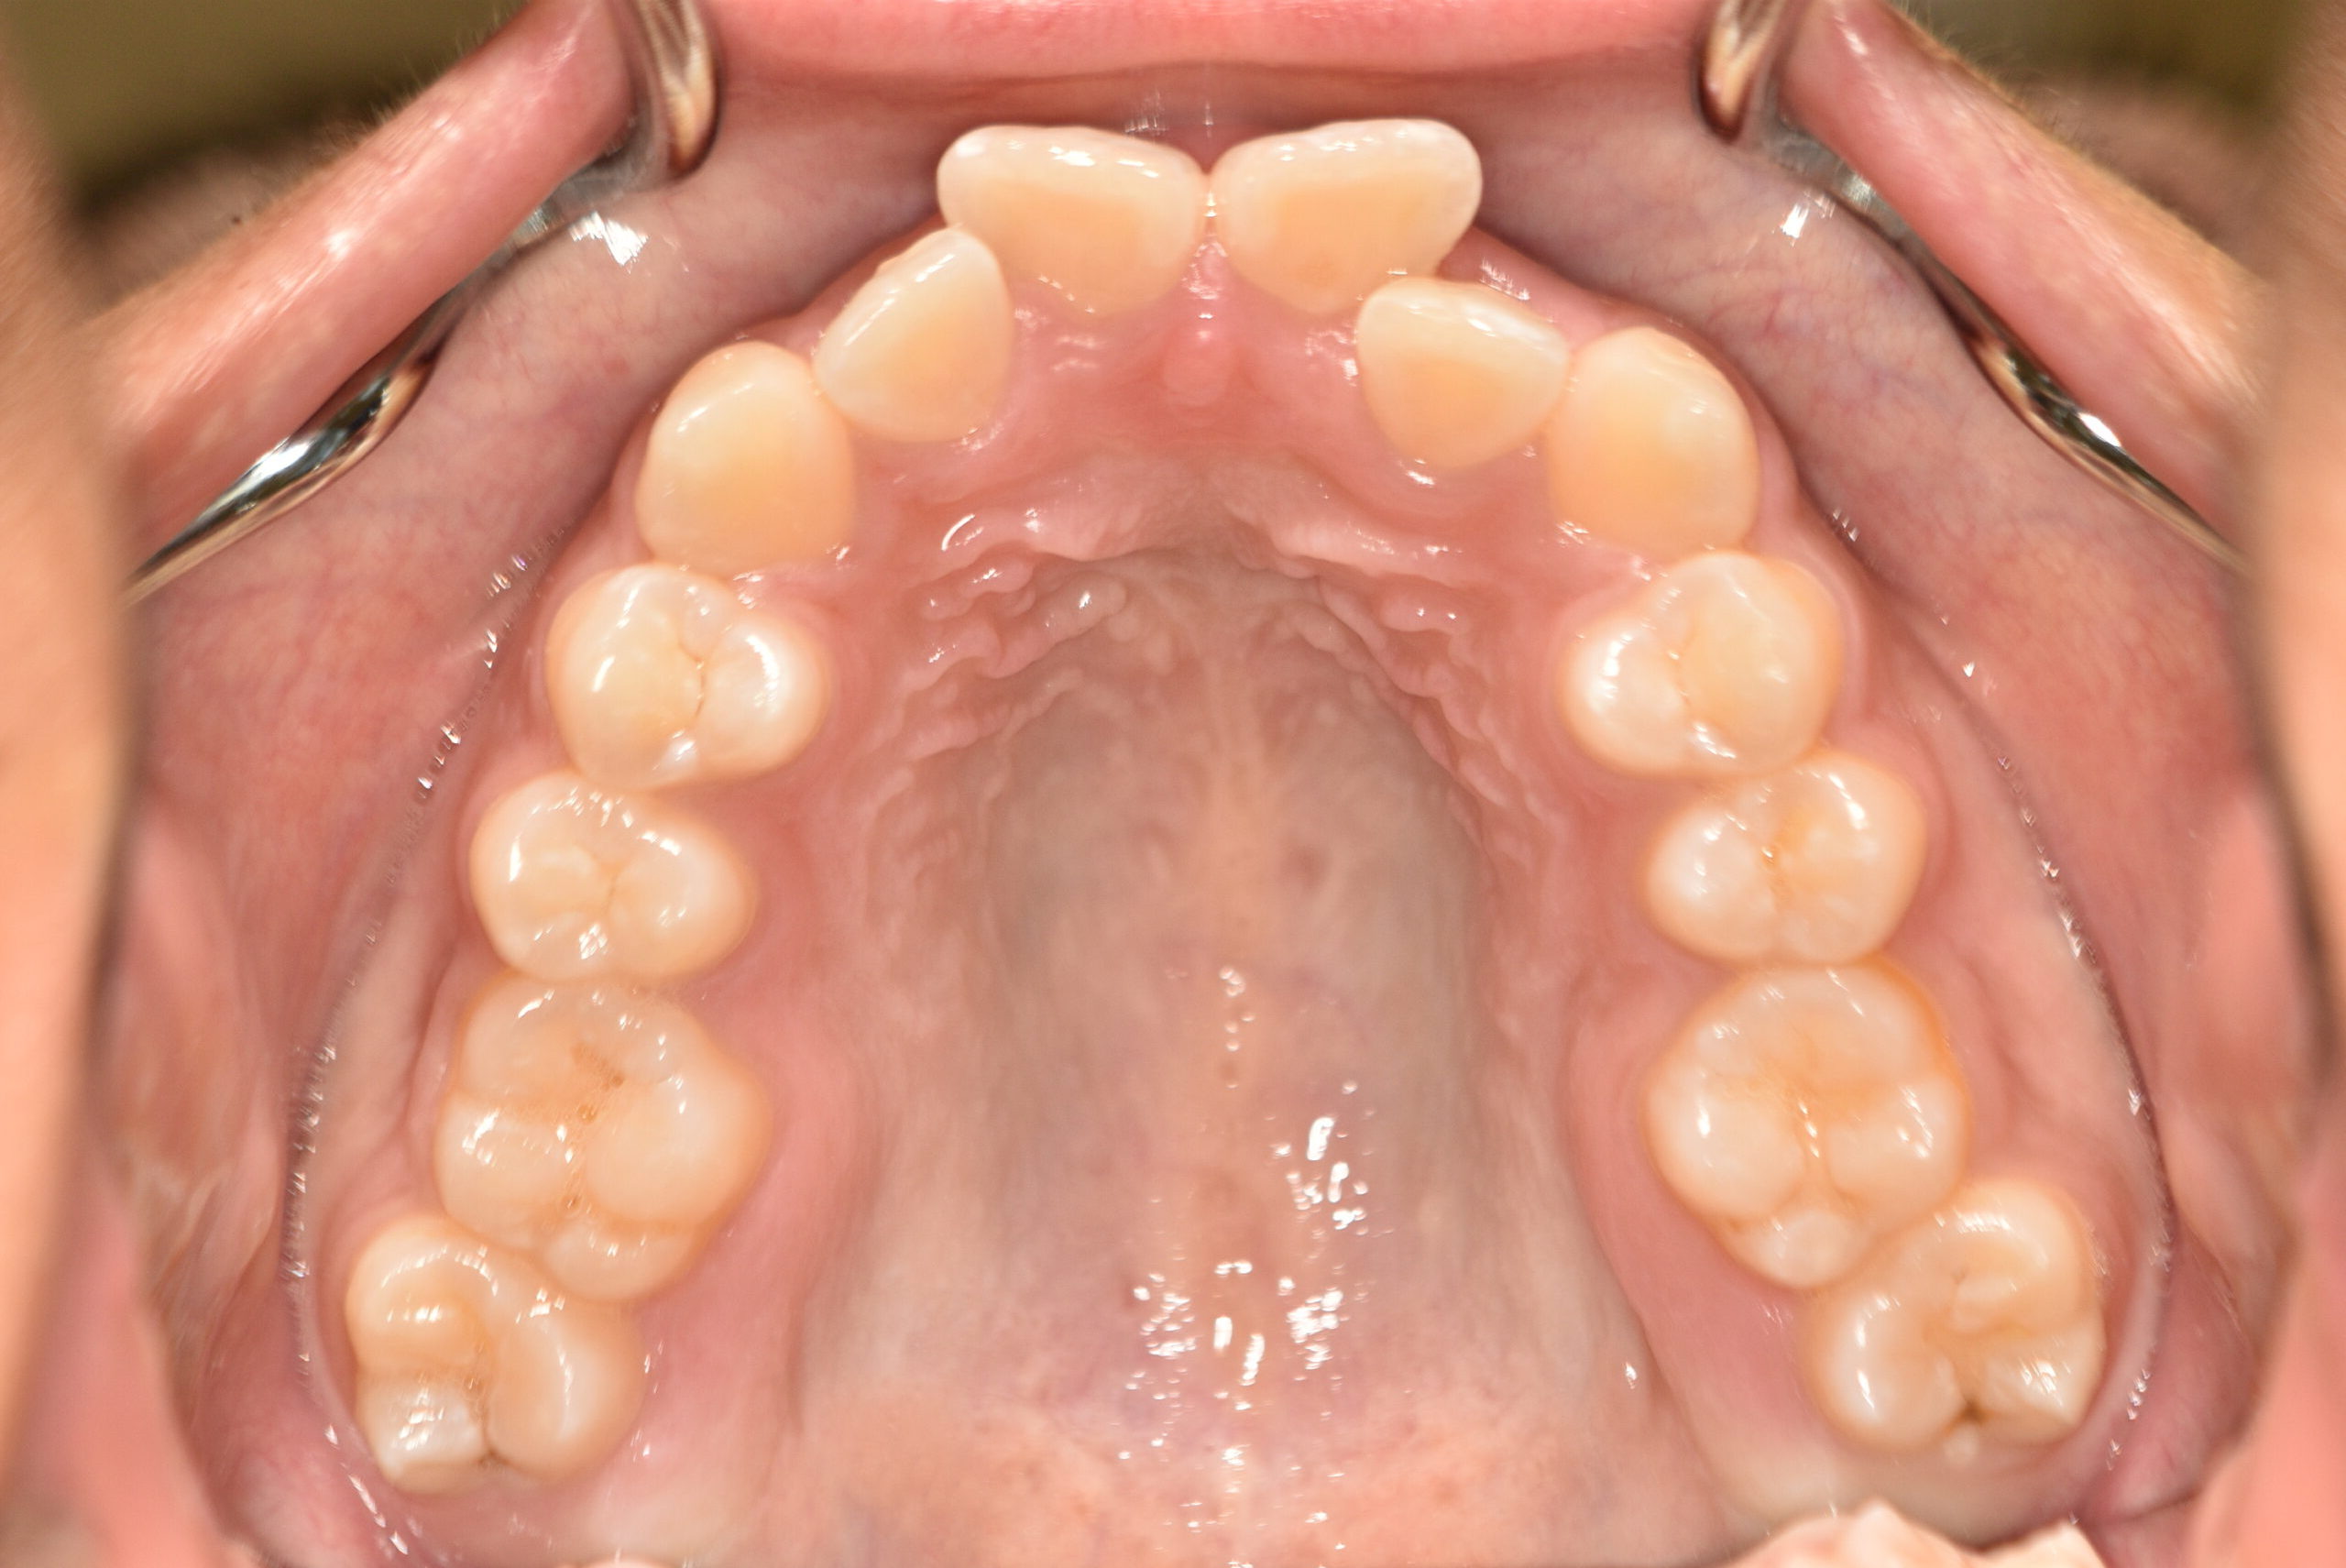

| 治療内容の詳細 | 初診時14歳の女性で、歯のがたつき、かみ合わせを気にされ来院されました。 検査の結果、上下顎前歯部叢生および開咬を伴うアングルⅠ級不正咬合と診断しました。 治療としては、非抜歯の上、セルフライゲーションブラケット装置(デーモンシステム)と マウスピース矯正装置(インビザライン)で配列を行いました。 開咬については、顎間ゴムの協力もあり改善されました。 治療期間は、2年2ヶ月でした。 |